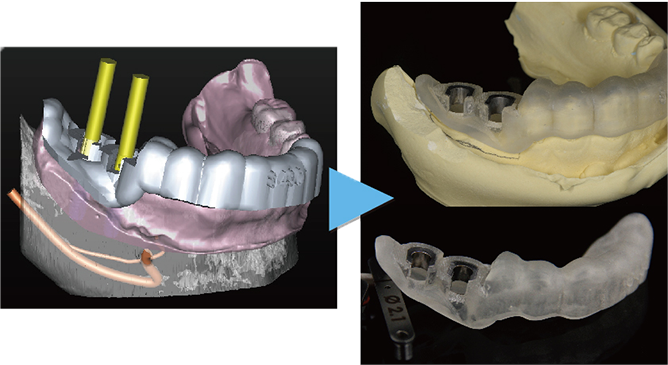

「シンプラント プロ」で計画されたシミュレーションデータからサージガイドを作製します。

作製されたサージガイドをお口の中に装着して手術を行うことにより、計画した位置をお口の中に正確にトランスファーしてインプラント手術することができます。

理想的な位置に計画された3DデータからCAD/CAMで高精度なサージガイドを作ります

治療前のシミュレーション

施術前のレントゲン

サージガイドを使用することによって計画された位置に正確な施術が可能です

― 治療後 ―

計画した位置に正確に施術することで良好な審美結果が得られます